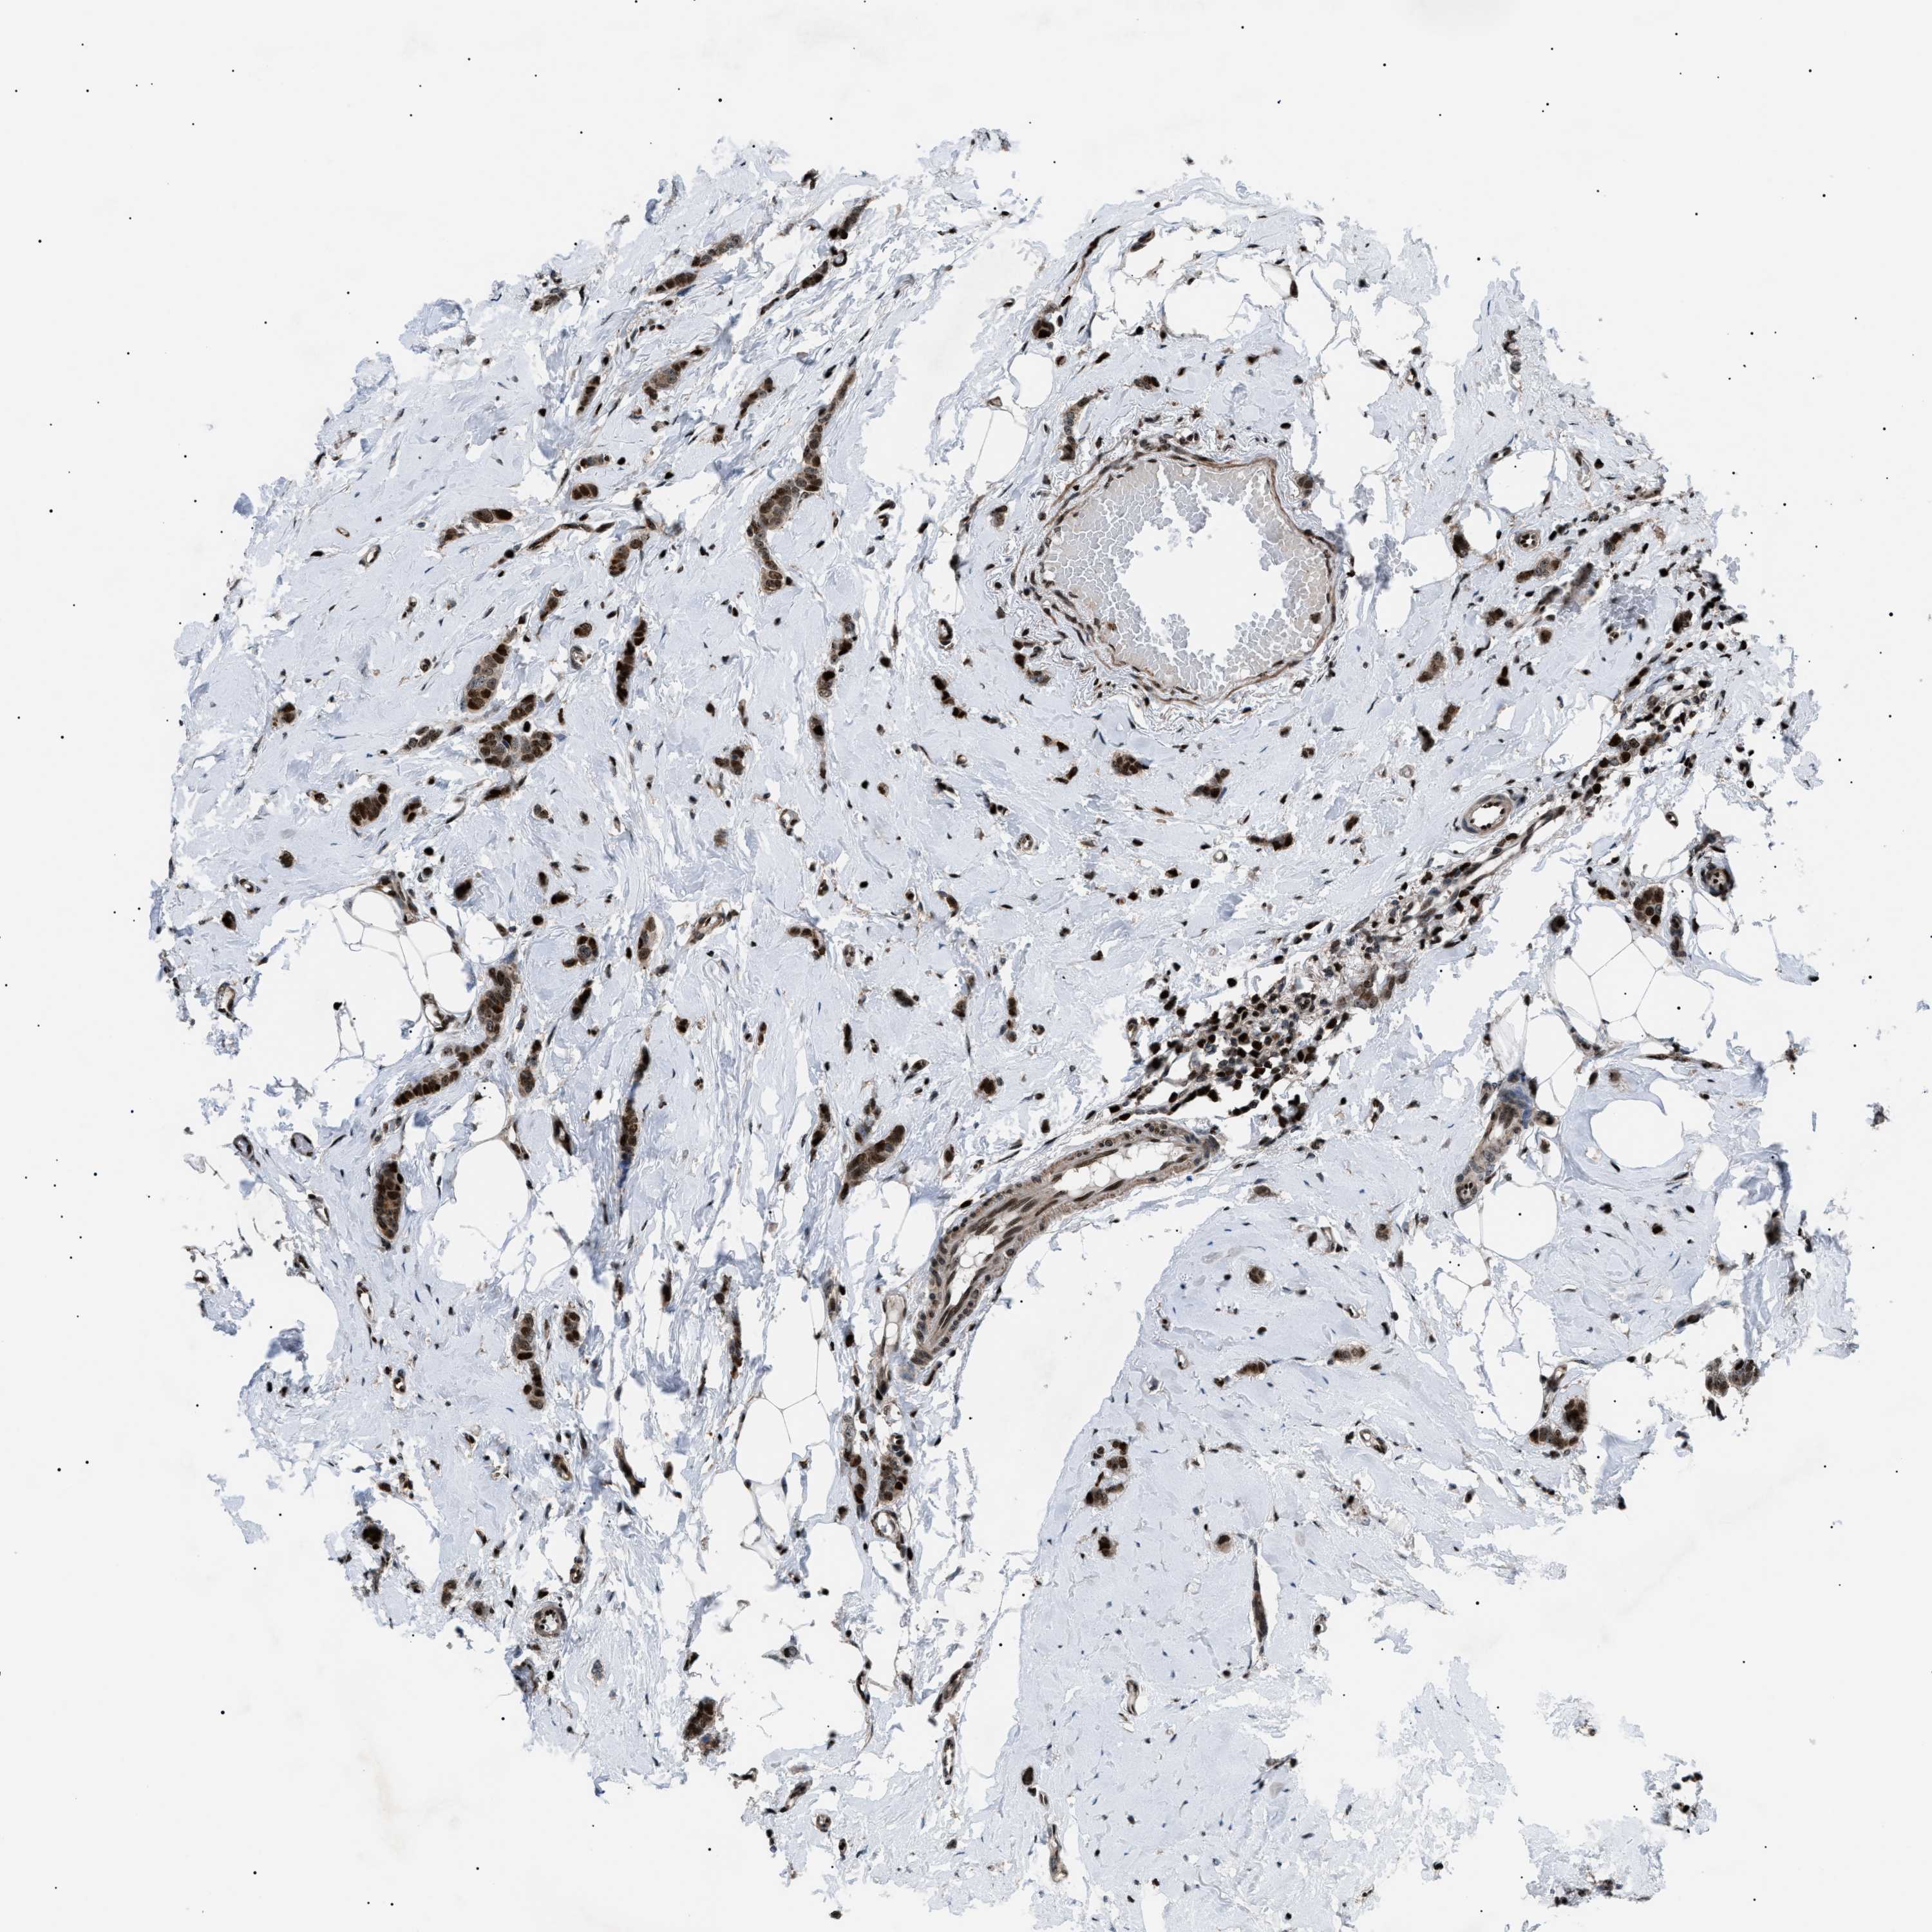

CANCER BREAST CANCER Show tissue menu

BRCA TCGA BRCA VALIDATION PROTEIN EXPRESSION

ANTIBODIES

AND

VALIDATION